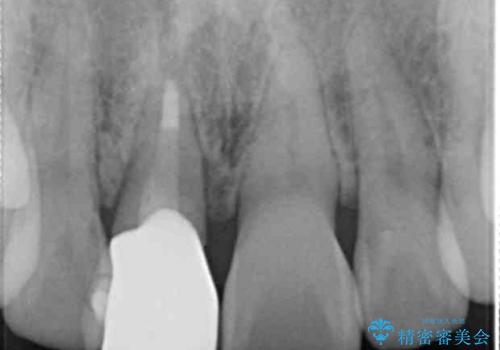

- 幼少期に前歯をぶつけて歯が折れ、神経の治療・クラウン治療を行った。グラつきと見た目の改善を希望して来院されました。

精密な仮歯をいれ、歯周組織を整えるとともにファイバーコア築盛、シェードテイキングを行い見た目に自然なジルコニアクラウンを製作していきます。